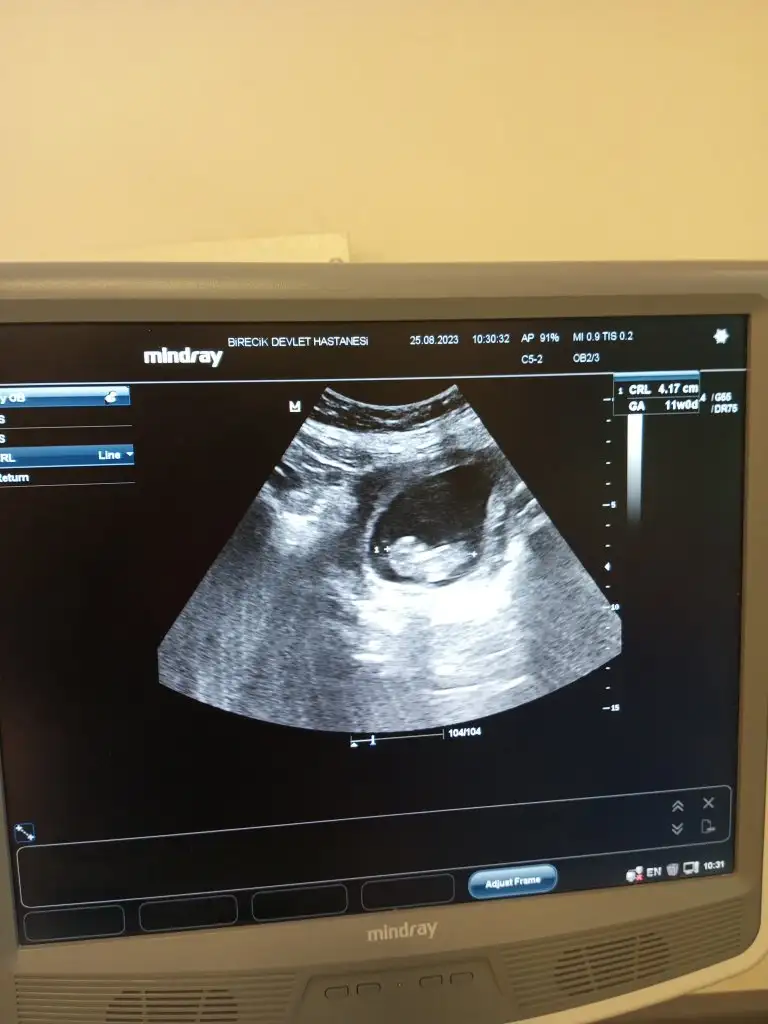

11+1 ve 11+4 haftalıkken size göre cinsiyet nedir?%90 erkek

Erkek bence hayirlisiyla alin kucaginiza11+1 ve 11+4 haftalıkken size göre cinsiyet nedir?

Bir erkek dediler, bir kız en son kızda kaldı değişme olursa söylerim size.Erkek bence hayirlisiyla alin kucaginiza

Çok teşekkür ederim. Hepimiz hayırlısı ile ve sağlıkla alalım kucağımıza inşallahErkek bence hayirlisiyla alin kucaginiza